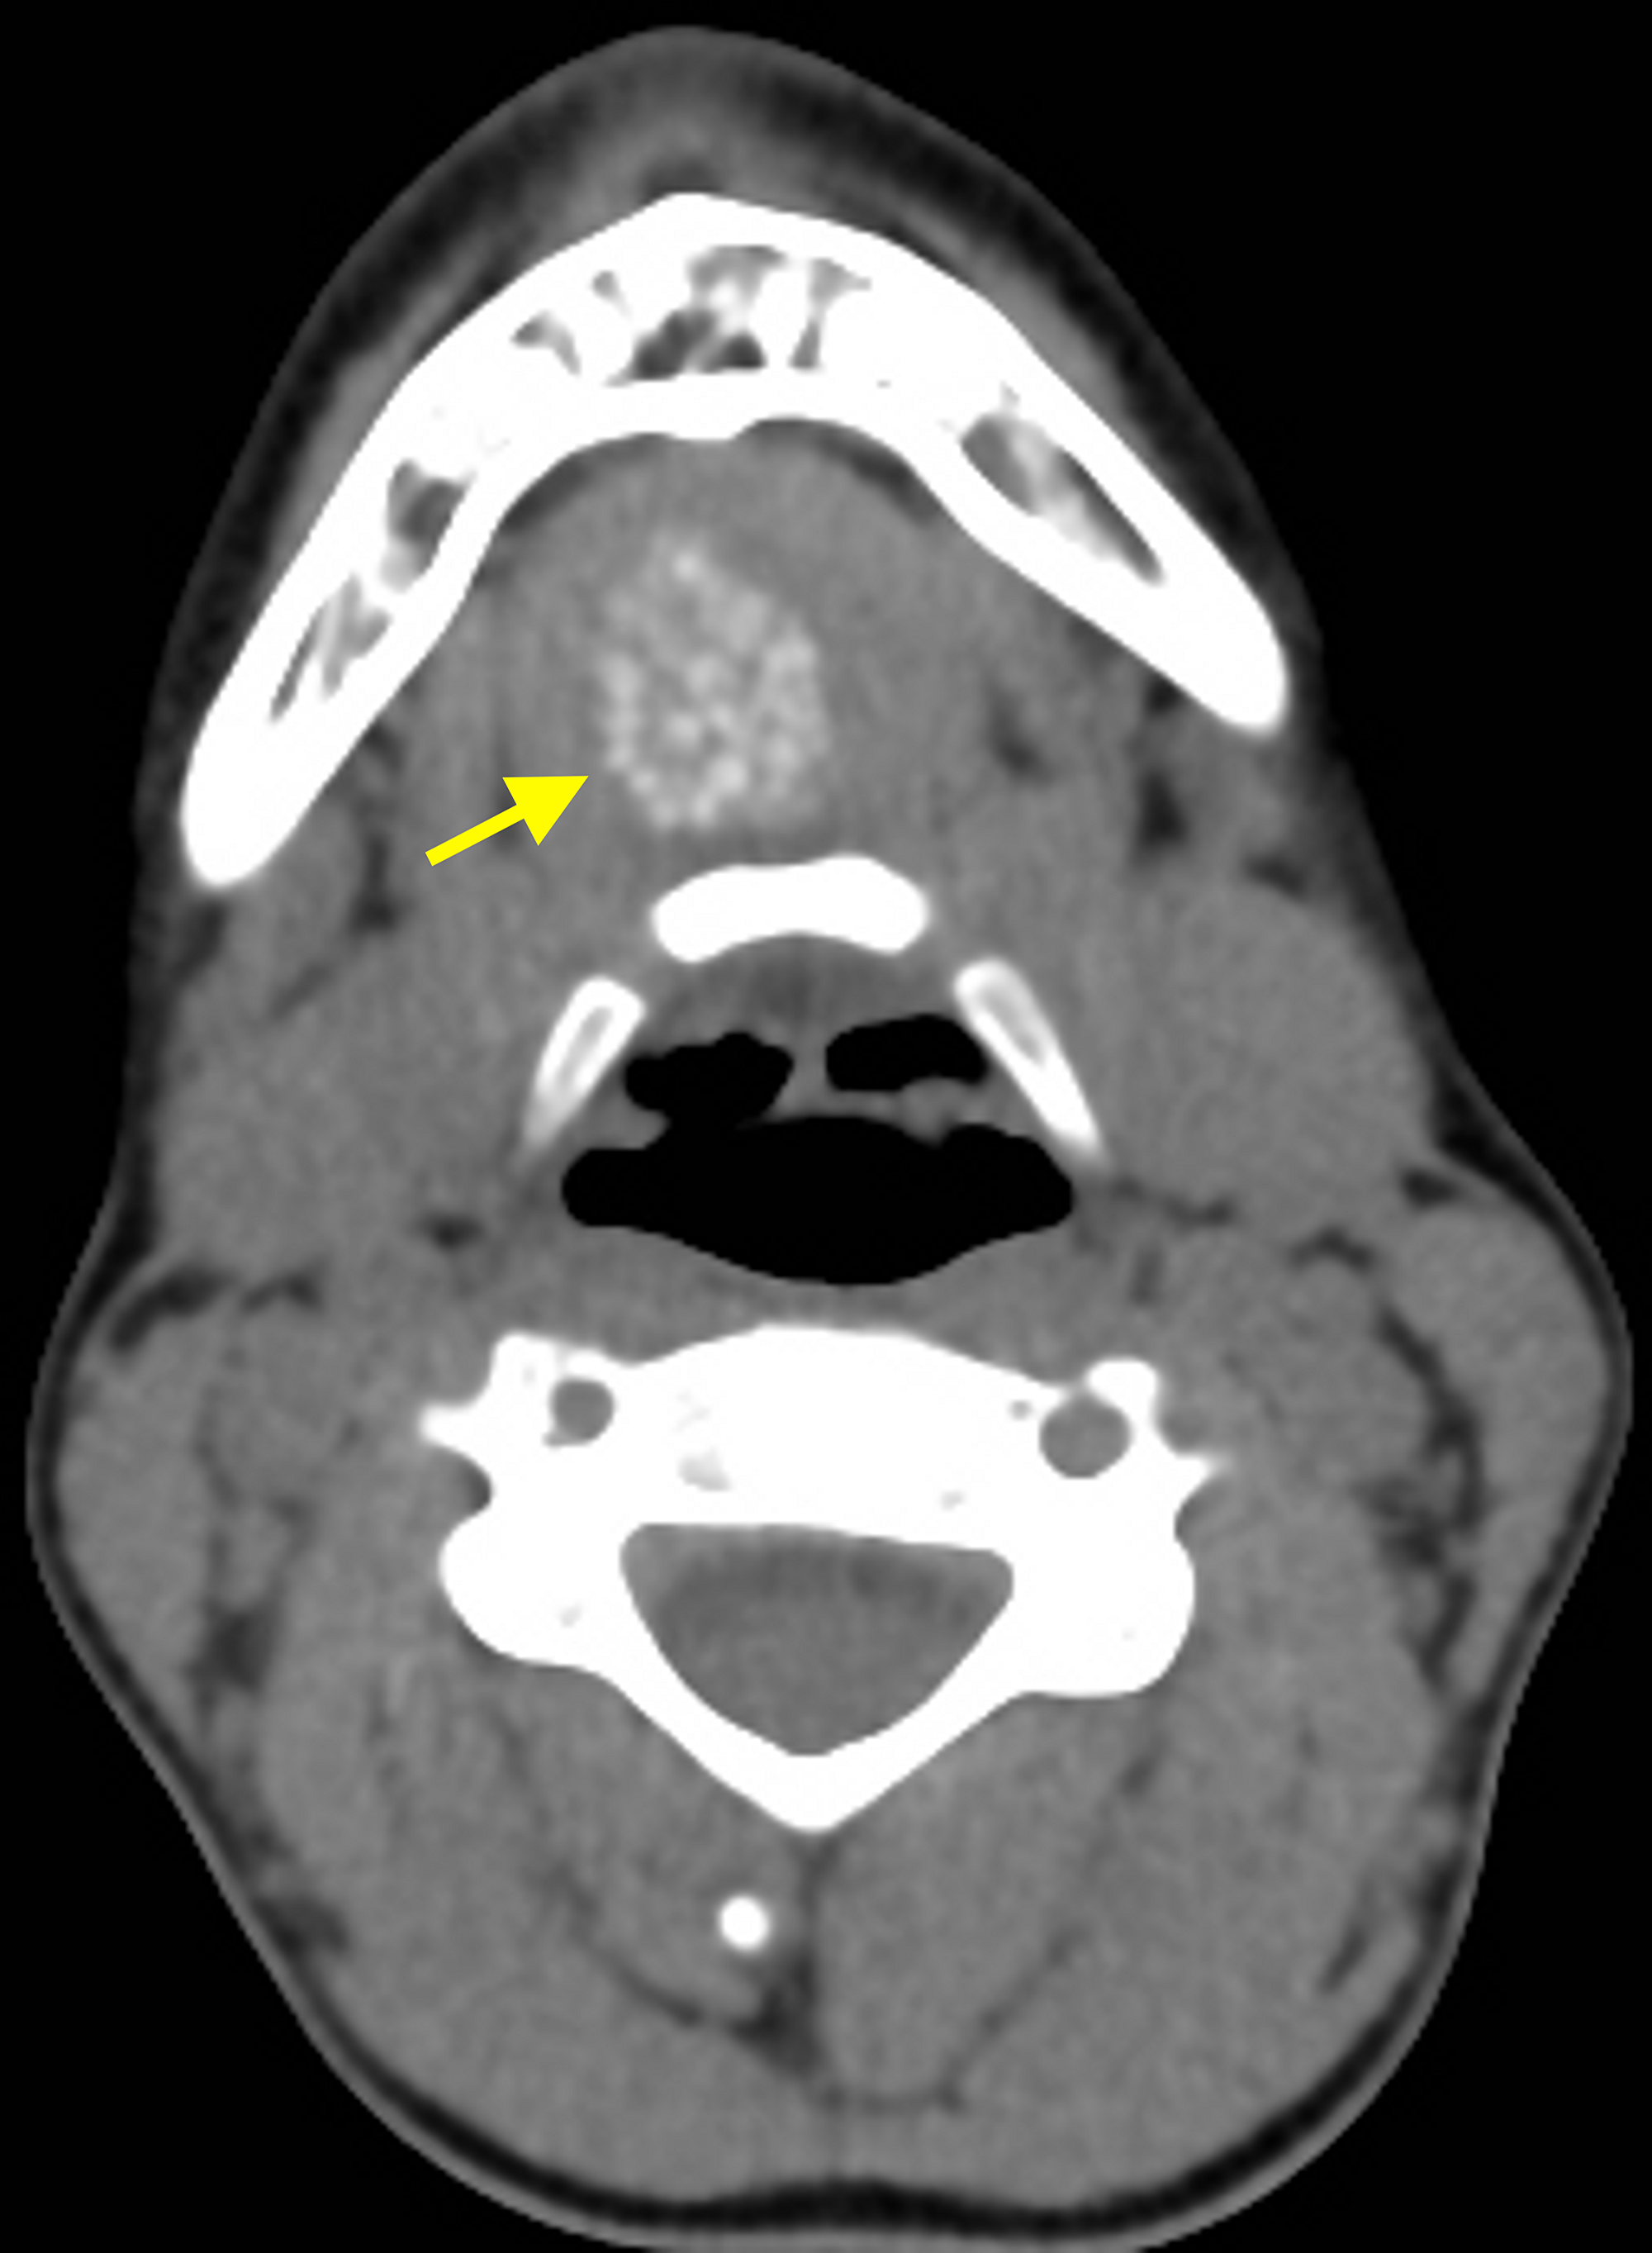

• the oral cavity consists of the upper and lower lips, gingivobuccal sulcus, buccal mucosa, upper and lower gingiva (including alveolar ridge), hard palate, floor of the. Imaging of the oral cavity can be limited by artefacts from dental amalgam and opposed. Anatomy, definitions, functions and innervation of the. The term root of tongue should not be. The root of tongue is the deeper anatomical part of the tongue contained in the oral cavity. The floor of mouth is an oral cavity subsite and is a common location of oral cavity squamous cell carcinoma. Fully labeled illustrations and diagrams of the buccal cavity: Familiarity with the radiologic anatomy and landmarks of the floor of the mouth is helpful for detecting and characterizing.

Review of imaging anatomy and pathology of the floor of the mouth Mouth Anatomy Mri Fully labeled illustrations and diagrams of the buccal cavity: The root of tongue is the deeper anatomical part of the tongue contained in the oral cavity. Imaging of the oral cavity can be limited by artefacts from dental amalgam and opposed. Anatomy, definitions, functions and innervation of the. • the oral cavity consists of the upper and lower lips, gingivobuccal. Mouth Anatomy Mri.

Imaging the Floor of the Mouth and the Sublingual Space RadioGraphics Mouth Anatomy Mri The floor of mouth is an oral cavity subsite and is a common location of oral cavity squamous cell carcinoma. Anatomy, definitions, functions and innervation of the. Fully labeled illustrations and diagrams of the buccal cavity: The term root of tongue should not be. Familiarity with the radiologic anatomy and landmarks of the floor of the mouth is helpful for. Mouth Anatomy Mri.